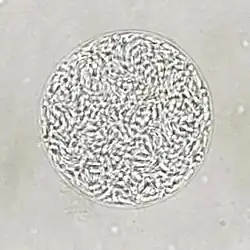

Giemsa stained T. gondii tachyzoites, 1000× magnification | |